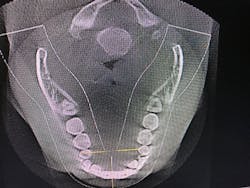

After identifying Danny’s history and evaluating the clinical signs, we moved to screening and testing. We recommended a home sleep test for his airway and breathing problems, as well as a Doppler auscultation and CBCT imaging for the TMD and occlusal issues.

The Doppler auscultation revealed reciprocal click on the left temporomandibular joint. The CBCT revealed normal joint anatomy, nasal airway obstruction with a slight deviated septum, and approximately 95% tonsillar obstruction in the posterior throat region. These findings led us to the conclusion of a positive airway/breathing disorder, with a Piper Stage I right temporomandibular joint and Piper Stage IIIa left temporomandibular joint.